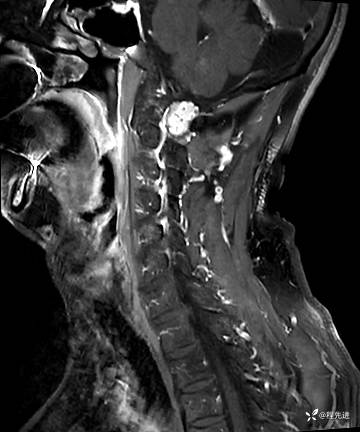

MRI平扫+增强:

T2: